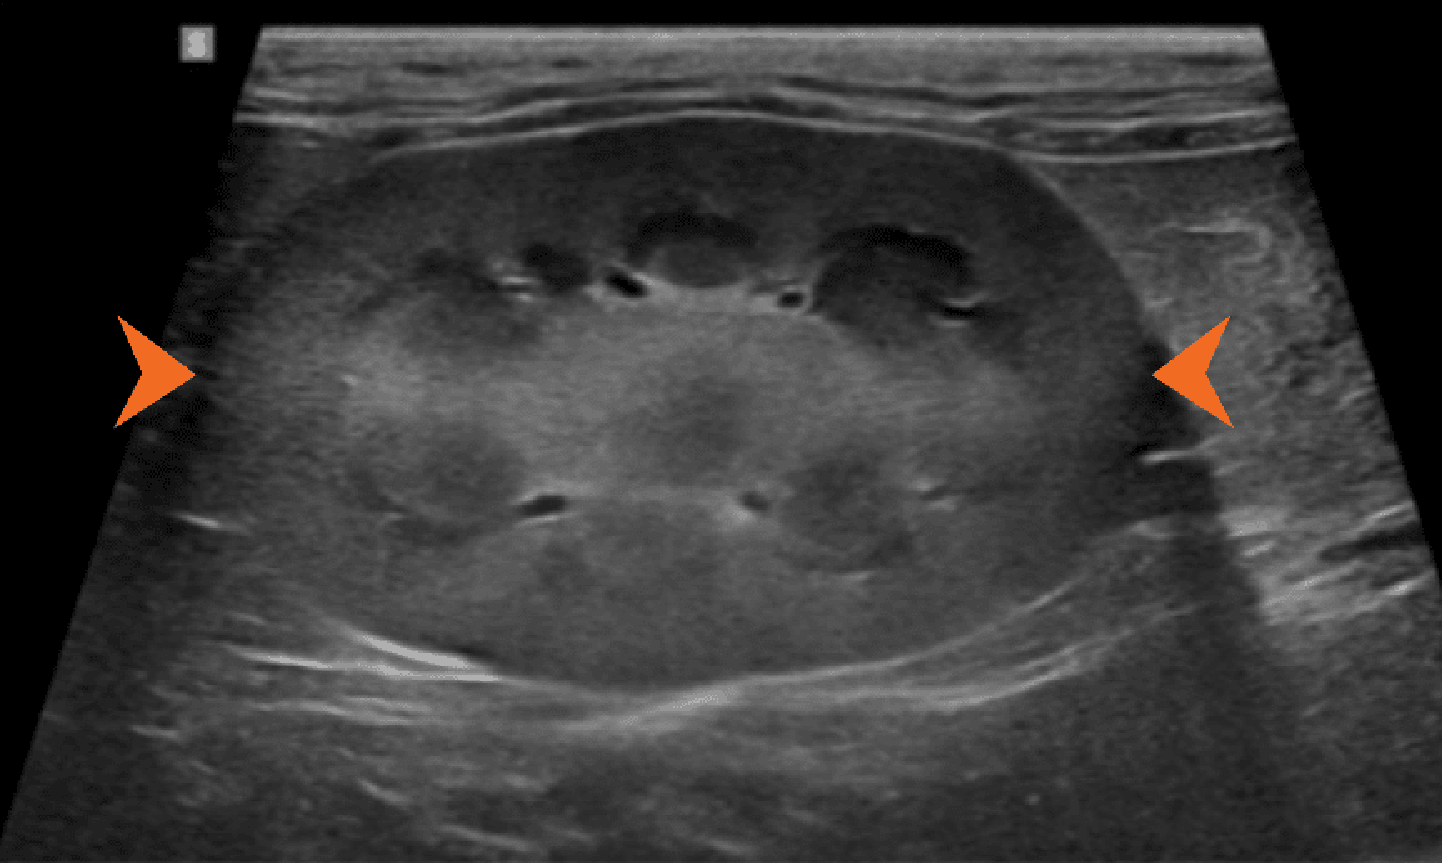

Ryc. 1. Obrazy ultrasonograficzne prawidłowej nerki kota w projekcji: a) strzałkowej, b) dogrzbietowej oraz c) poprzecznej. Towarzyszące ilustracje przedstawiają przebieg płaszczyzn obrazowania.

Ryc. 2. Obraz w projekcji strzałkowej prawidłowej lewej nerki psa, ukazujący hiperechogeniczny zewnętrzny pas rdzeniowy (groty strzałek).